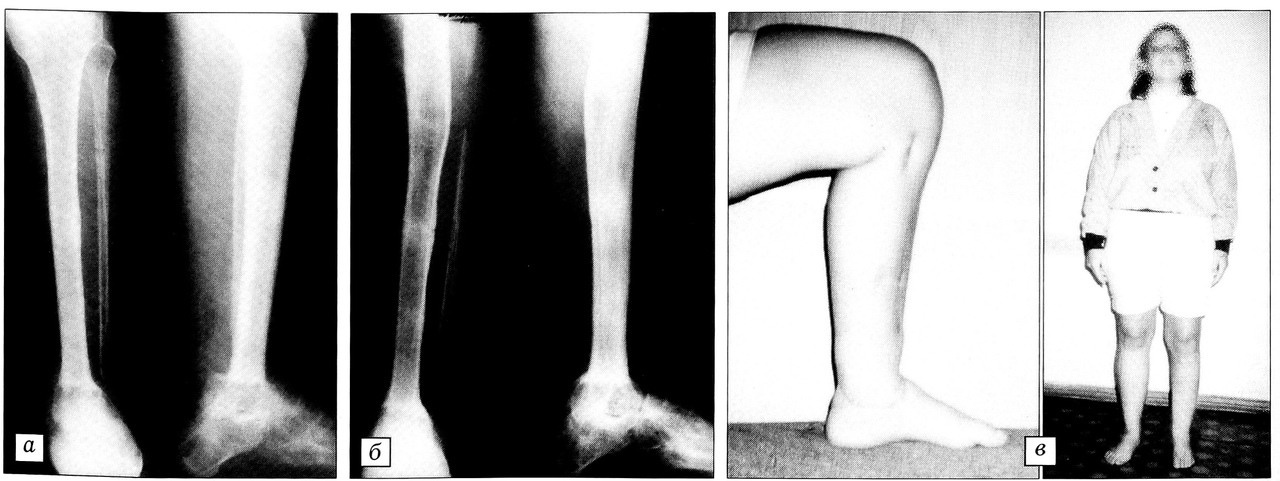

Рис. 2. Больная Е. Полное отчленение сегмента нижней конечности. а-рентгенограммы через 1 год после реплантации отчлененного сегмента (укорочение конечности на 11 см); б — рентгенограмма, в — внешний вид и функция конечности через 3 года после реплантации и 2 года после начала удлинения голени.

Больная Е.,26 лет, поступила в клинику через 12ч после отчленения нижней конечности на уровне нижней трети голени (железнодорожная травма). Была произведена реплантация отчлененного сегмента по описанной выше методике. Через 8 мес отмечено восстановление чувствительности стопы. Движения в пальцах стопы в пределах 30°. Гипсовая повязка снята через 4 мес — после консолидации костей. Укорочение конечности составило 11 см (рис. 2, а).

Через год после реплантации произведено удлинение конечности на 6 см по описанной выше методике. Еще через год (спустя 2 года после реплантации) предпринято повторное удлинение костей голени на 5 см. Общая величина удлинения составила 11 см. Через 2 года после второго этапа удлинения функция конечности восстановлена (рис. 2, б, в).